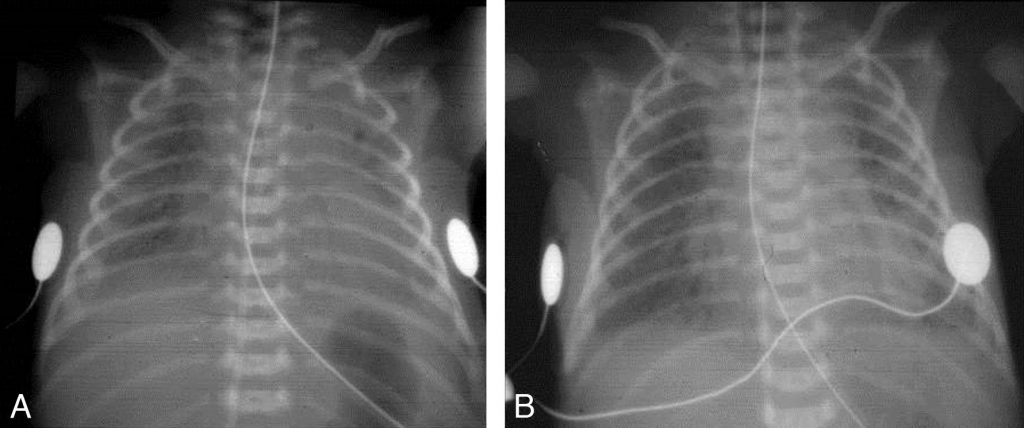

La radiographie thoracique objective un petit volume pulmonaire, des suropacités alvéolaires, allant du granité jusqu’au poumon blanc, avec bronchogramme aérien. Après instillation endotrachéale de surfactant, les poumons sont rapidement mieux ventilés, avec retour à une transparence pulmonaire normale (figure 124.1).

Fig. 124.1 Radiographie thoracique de face, couché.

Maladie des membranes hyalines (A). Même nouveau-né (B), après instillation endotrachéale de surfactant.

Source : CERF, CNEBMN, 2022.